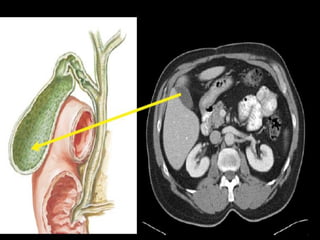

Gallbladder :

 lies in a fossa on the visceral surface of the liver to the right of

the quadrate lobe.

 It stores and concentrates bile, which enters and leaves through

the cystic duct. The cystic duct joins the common hepatic duct

to form the common bile duct.

3/22/2024 27